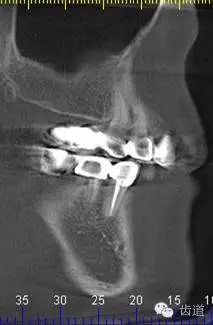

5、右下頜側(cè)面觀

6、45,46,47牙片

7、45,46,47CBCT